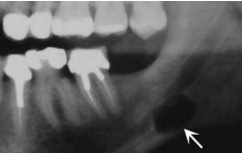

| Odontogenic Keratocyst cyst (OKC) |

下顎骨後端,下齒槽管上方 | 10-40y | 組生齒(40%) | |

| Radiolucent、 MD方向下顎骨吸收,但牙根完整。  |

|||||

| 4-8 層、副角化(有核)、Basal cell 為 palisaded(柵狀) | |||||

| 高復發 (30%) | |||||